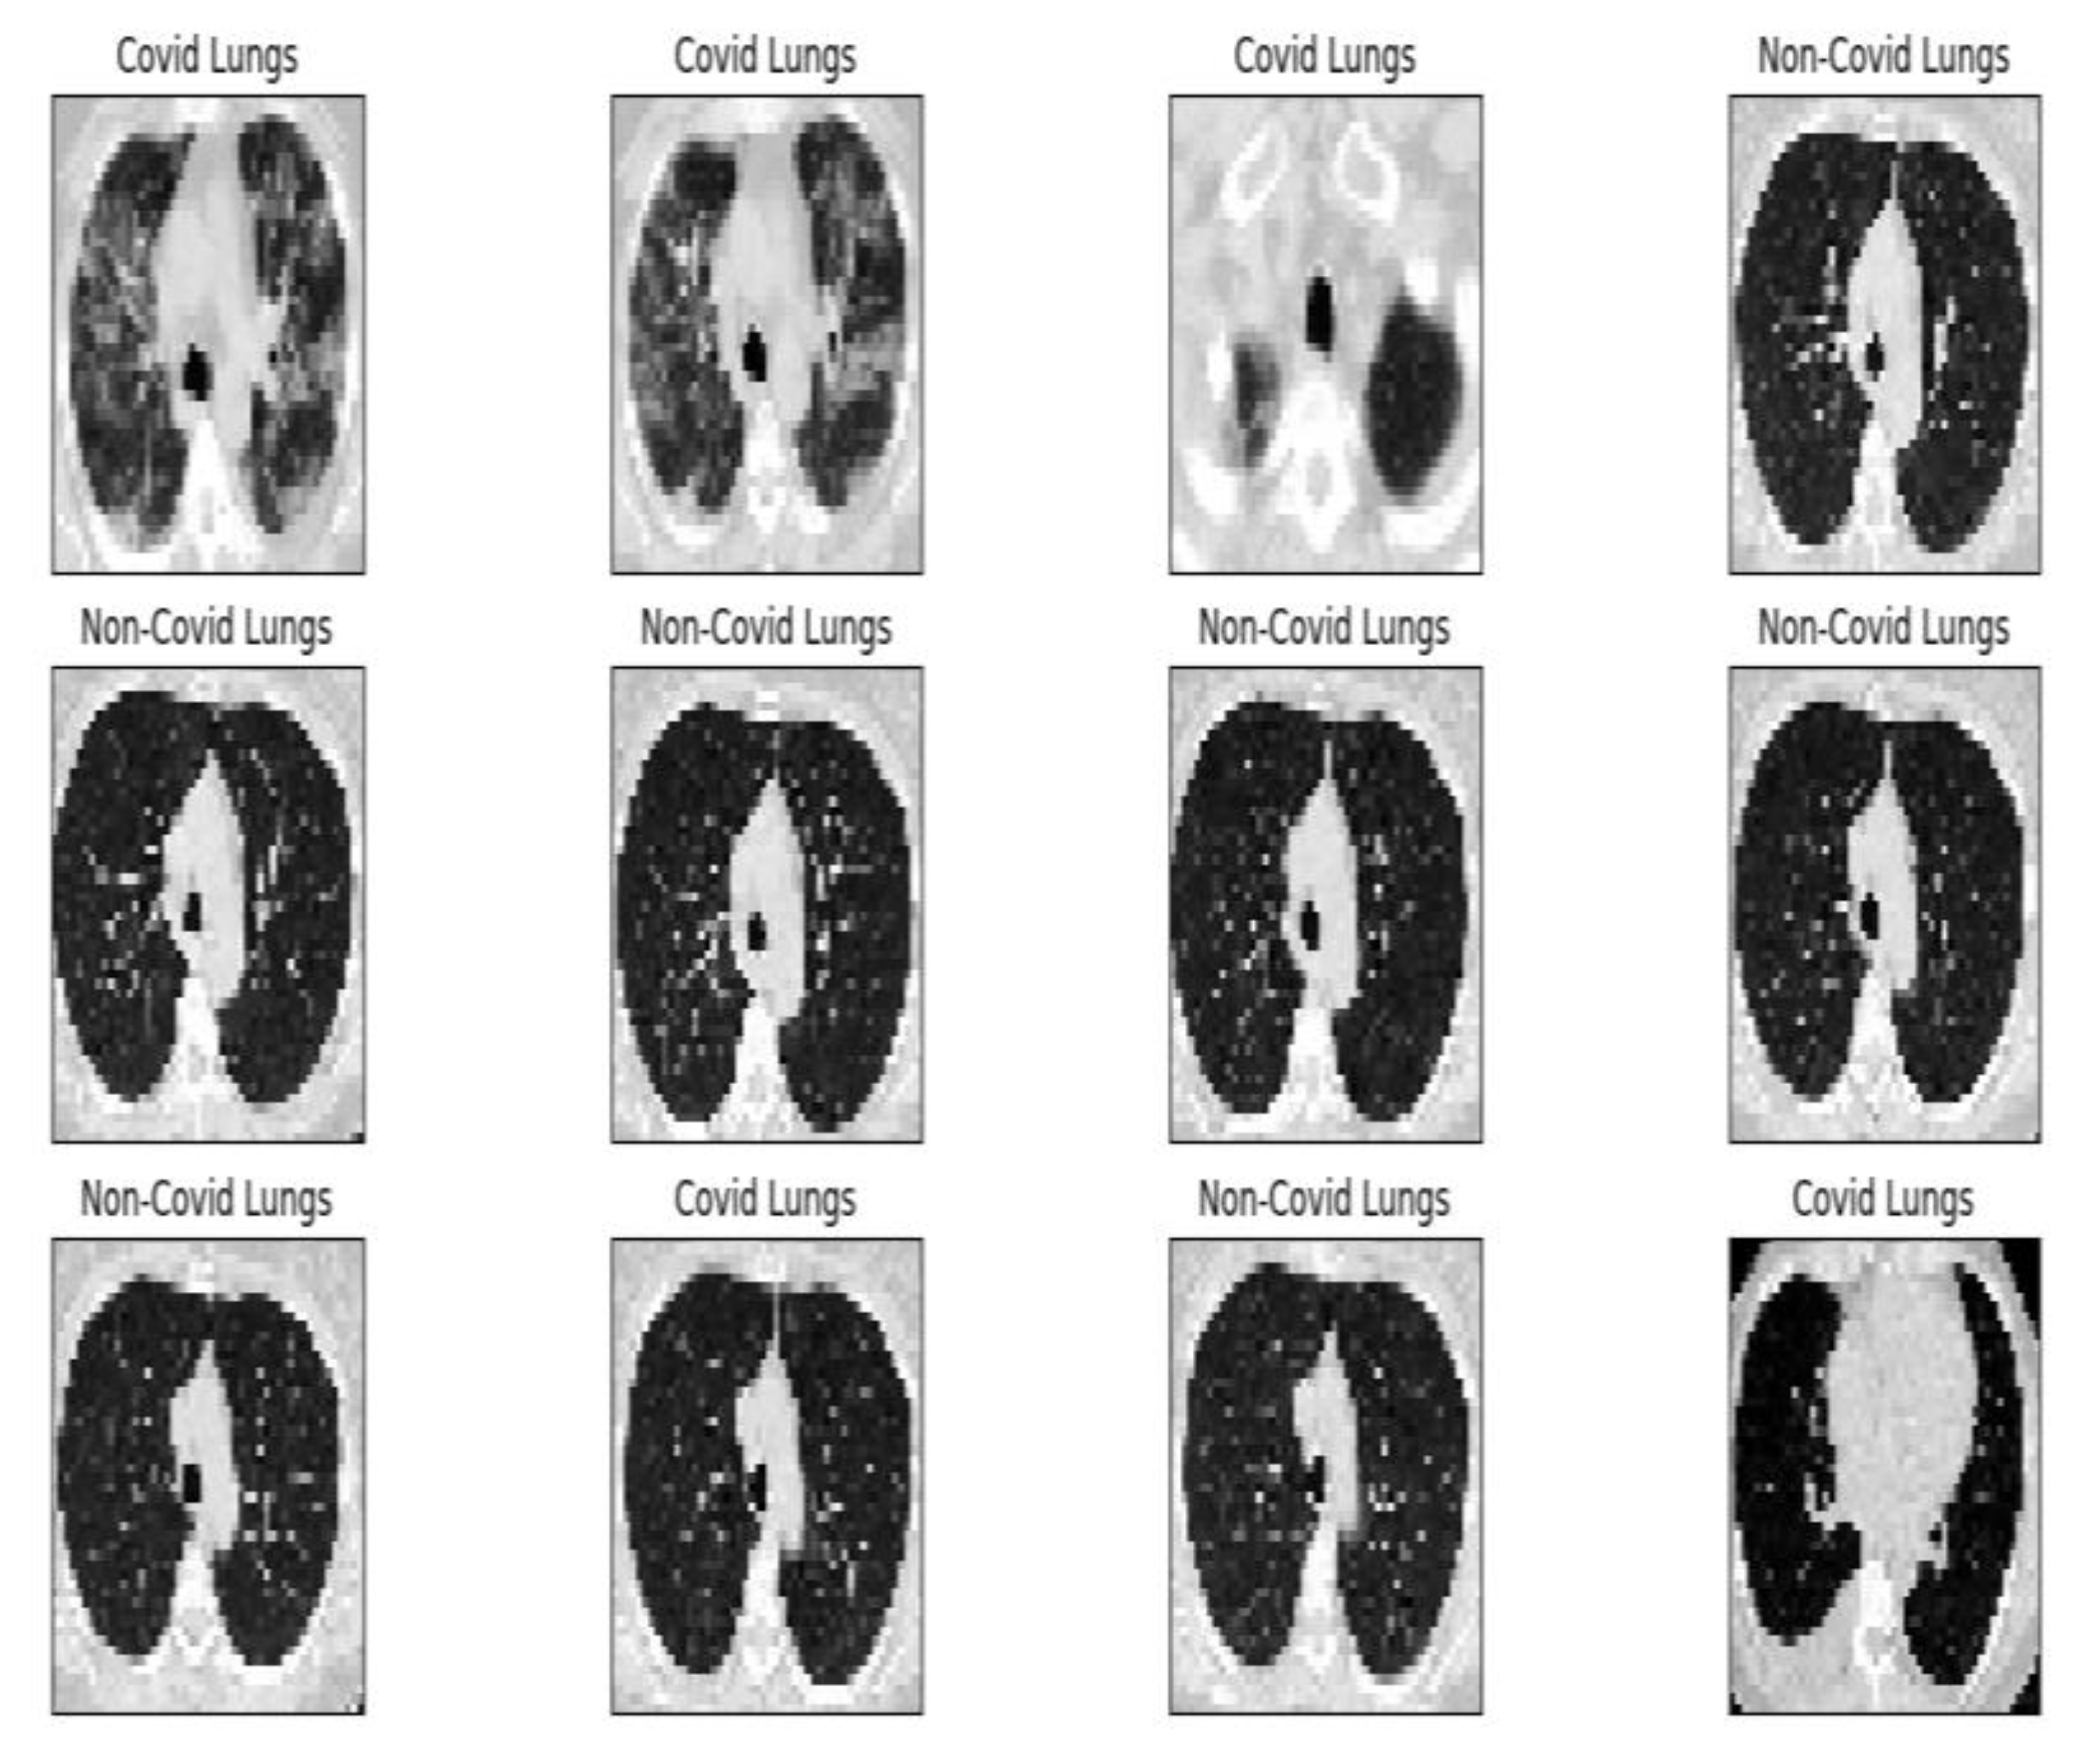

Project development started by establishing the data set according to the objective. For this, we used a public data set provided by the www.kaggle.com platform. The set comprises 2481 images (1251 contain lungs with COVID-19 infection and 1230 contain lungs without COVID-19 infection). At the beginning of the program, each image receives the appropriate label, “covid” or “normal”, which is resized to 50 × 50 pixels (see Figure 2) and undergoes conversion to grayscale (grayscale format). After these transformations, the image–label pair is passed as an entry in an array. Further, a block list containing the values of the main parameters used in the inference process is presented in Figure 3.

Figure 2 is the block diagram for the inference process of the AI procedure. The simple distributed AI network is based on an input CT image, having two direct distributions for COVID-19 patients and, respectively, for non-COVID-19 patients [16].

Figure 2 is a block diagram of the application.

Figure 8 shows the complete module of some lung CT images affected by COVID-19 and images of lungs that did not suffer from COVID-19, unaffected by the virus, practically healthy lungs.

We mention that the set of images from Figure 8 and the license to use them can be found online at the address indicated in the bibliographic reference [21].